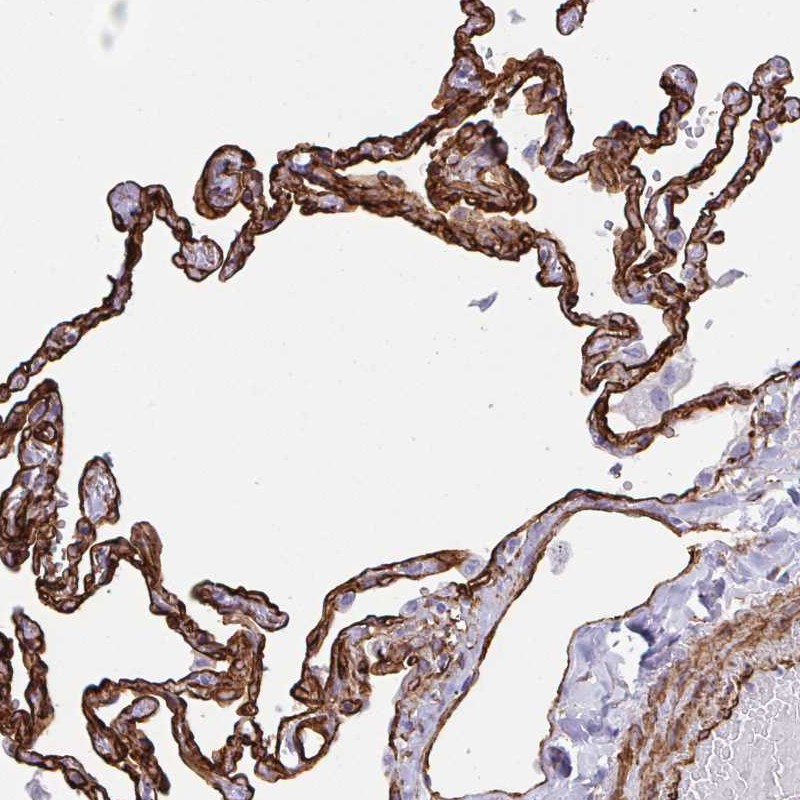

Immunohistochemical staining of human lung shows strong membranous positivity in pneumocytes.